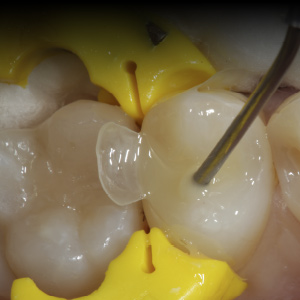

Materials and Techniques to Improve Class II Composite Restorations

Wednesday, June 26, 2019

Every day in dental practices all over the world, dental professionals complete one of the most common dental restorations: Class II direct composite restorations. However, Class II direct composite restorations can present numerous challenges. This article will cover Class II composite restorations...